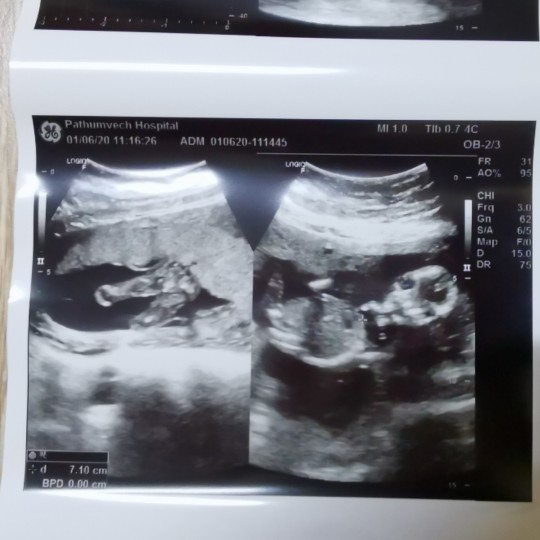

พศฤจิกายนจ้าาา. ลูกชาย

กำหนดคลอด 10 พฤศจิกายน.